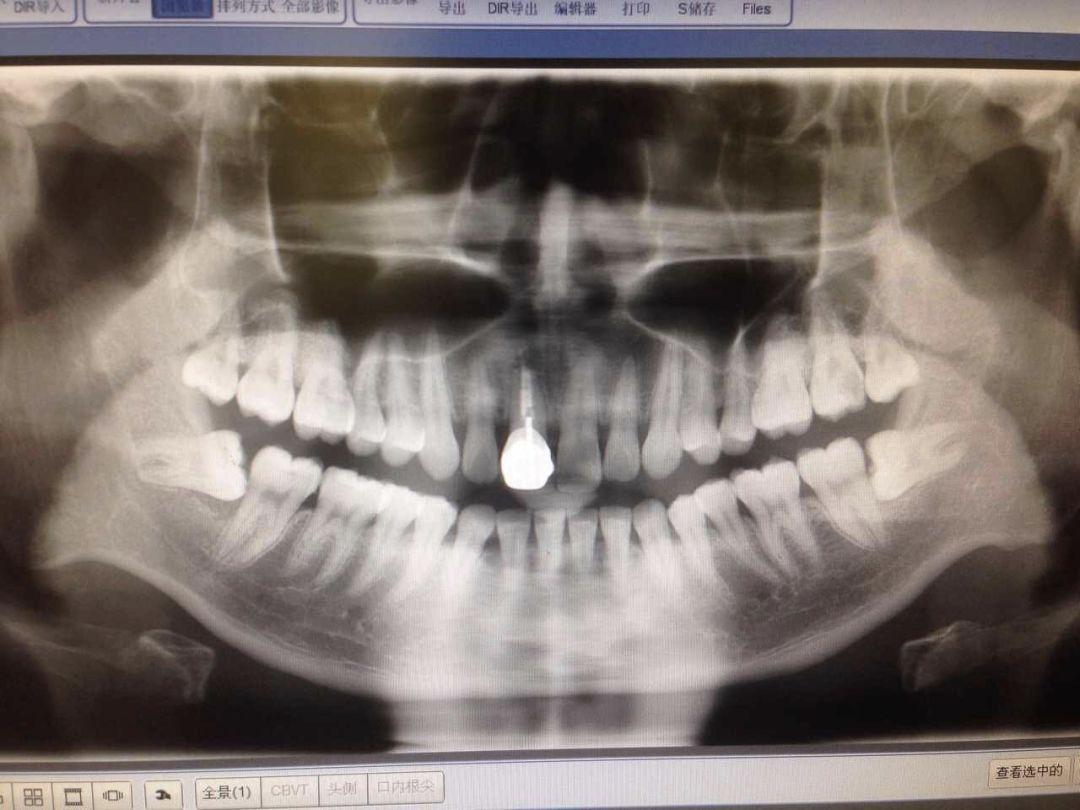

智齒有不同的長(zhǎng)法,我們今天按照 easy - normal - hard - hell 這 4 種難度等級(jí)來(lái)介紹…在拔智齒之前,一般要簽署一個(gè)手術(shù)知情書(shū)。拔智齒和普通拔牙不一樣,這都已經(jīng)算是外科手術(shù)對(duì)待了。首先是拍個(gè) 2 維的 X 片或是更精細(xì)的三維的 CT,確定智齒的位置和模樣,牙醫(yī)才能確定拔除方案(和價(jià)格)...

來(lái)帶領(lǐng)大家一起重溫下小編這張牙片,兩顆下智齒都是躺在牙床里的,有一點(diǎn)點(diǎn)頭露出來(lái),和旁邊的牙齒就形成一個(gè)不容易刷到的面。